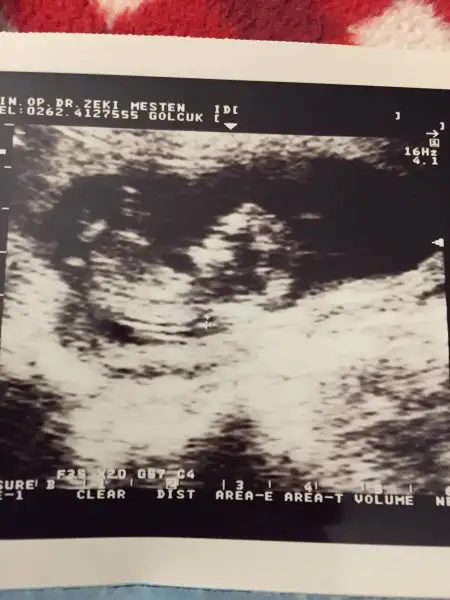

Kızlar ilk oğlumun usg lerini buldum fikir olsun diye paylaşıyorum tüm yüz hatları ağız dudak çene göz çukurları bile belli gerçekten erkek bebekler daha belirgin oluyor sanırım yinede usg cihazından olabilir bilmiyorum bu usg 9 sene öncesi